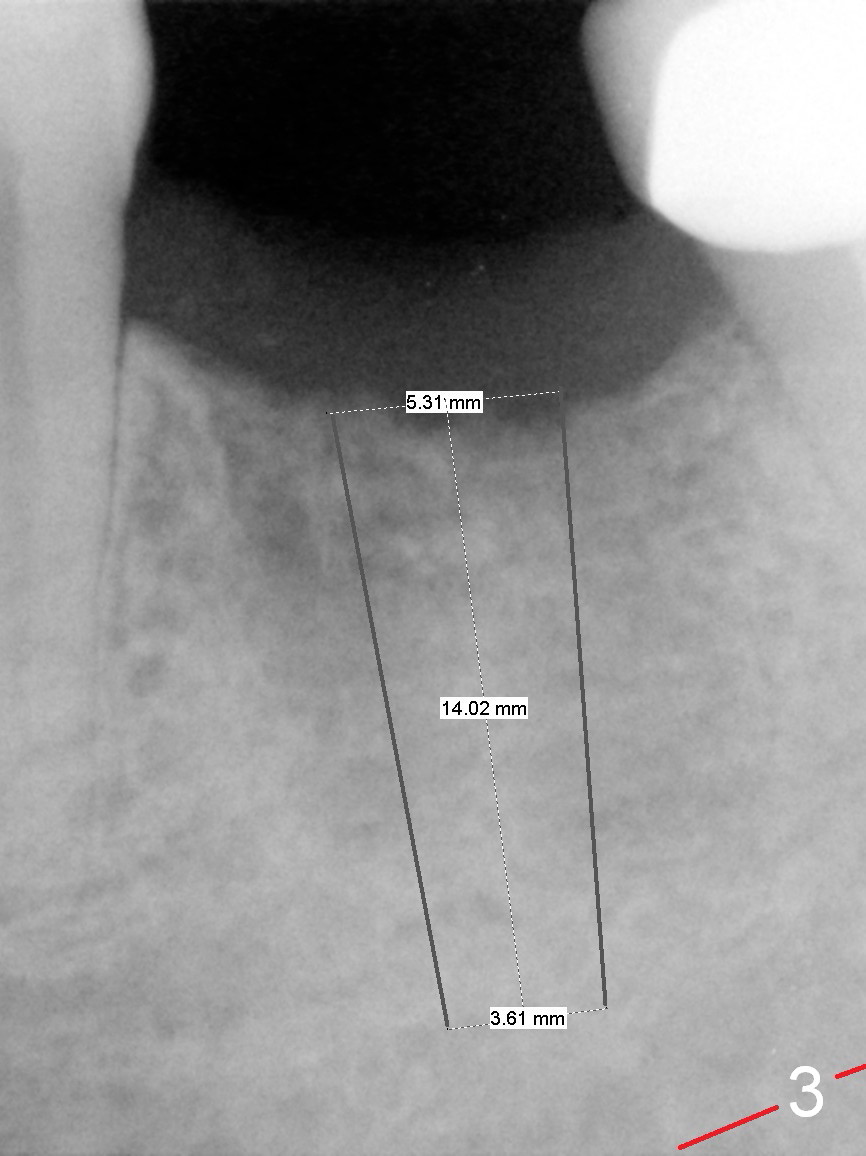

A 68-year-old man had the tooth #19 extracted more than 6 months ago (Fig.1). When his wife has had an immediate implant placed, he decides to have his implant placed. After incision, use the 5 mm implant positioner to check the width of the crestal bone. If it is less than 6 mm, the implant length will be most likely 14 mm. Clinical exam has revealed moderate ridge atrophy. Anyway, the initial osteotomy is 12 mm. It should pass the apices of the mesial (M) and distal (D) sockets (Fig.2 ^) in the middle of the septum (as compared to Fig.1 S). If there is enough safety margin, the osteotomy depth will be set at 14 mm (Fig.3 (red dashed line: the superior border of the Inferior Alveolar Canal)). There is no indication for intraop localized use of antibiotic.